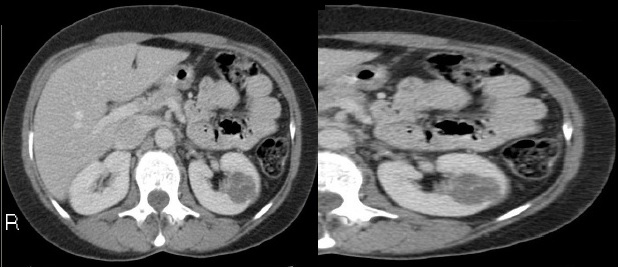

Fase corticomedular y arterial

Esta primera fase ocurre en los primeros 25 a 70 segundos posteriores a la inyección del medio de contraste; la corteza renal, al retener el medio de contraste en este tiempo en los capilares corticales aumenta de una manera intensa diferenciándose de la médula renal, que se encuentra hipodensa.

La fase arterial o corticomedular es esencial para la estadificación, extensión y planificación quirúrgica, si fuese el caso de la neoplasia encontrada, ya que ofrece un mejor detalle vascular (opacificación de los vasos), una mayor definición anatómica y de lesiones vascularizadas en el hígado, el bazo o el páncreas, consideradas dentro del contexto de una metástasis (Fig. 2).

Los errores diagnósticos que pueden presentarse durante esta fase se asocian a lesiones de pequeño tamaño; en el caso de un tumor hipervascularizado pequeño aumentaría su atenuación en la misma medida en que lo haría la corteza. Otro error que puede ocurrir es con los tumores pequeños que se localizan hacia la médula, ya que por su ubicación se mantendrían hipodensos durante esta fase 3-4.